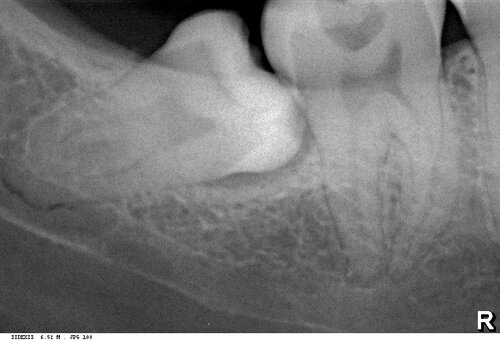

Даже если зубы мудрости не прорезаются — это не значит, что рисков осложнений нет. Фолликул, окружающий зуб, в любом возрасте может стать источником кисты — и в следующий раз придётся удалять не только зуб мудрости, но и вызванную им кисту. То есть, как раз тот случай, когда маленькая проблема превращается в большую или даже очень большую.

Во-вторых, обследование. Для удаления зубов мудрости в 99,9% случаев не нужна компьютерная томография, достаточно панорамного снимка. Всё, что нам нужно, на нём видно. Лабораторные анализы актуальны только в случае, если у вас есть серьёзные проблемы со здоровьем, и назначаются врачом-терапевтом по показаниям.

Так, между левой и правой фотографиями разница — не более 15 минут. Случай интересный, подробности здесь>>